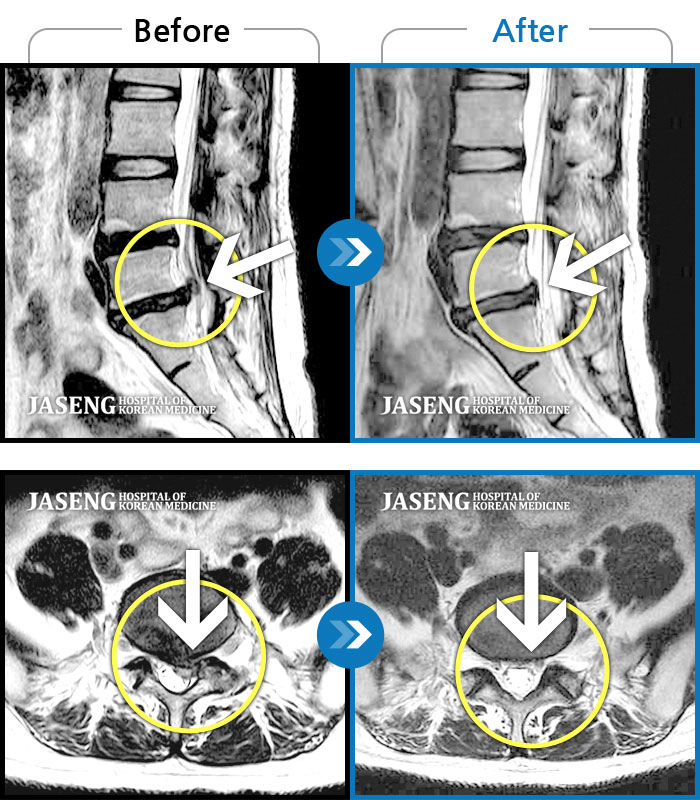

Before

After

환자에게 사전 동의를 받아 동일 조건에서 촬영되었습니다.

개인에 따라 치료 후 부작용이 발생할 수 있으니 의료진과 상담 후 치료를 진행하시기 바랍니다.